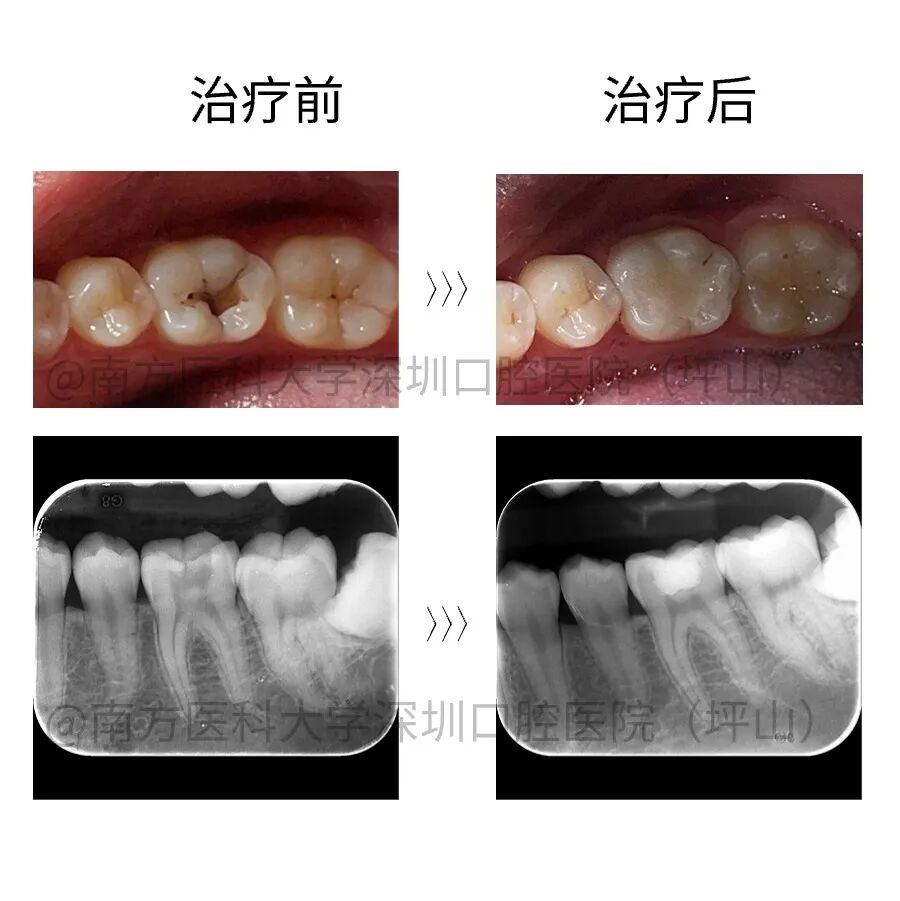

案例二

患者自诉右下后牙有洞,影像检查显示 47 牙深龋近髓,根尖未见异常。建议试行活髓保存治疗。一年后复查无异常。